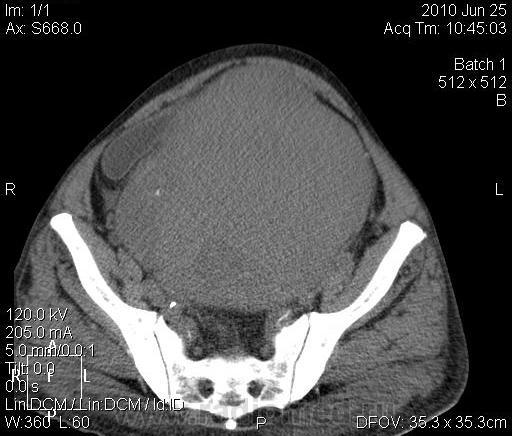

КТ. Забрюшинная опухоль. Лейомиосаркома. Вторичный гидронефроз.

Мужчина 79 лет, долгое время не обращался за медпомощью. Видимое внешне образование брюшной полости. По УЗИ: опухоль брюшной полости, двусторонний гидронефроз. Гемоглобин 136, СОЭ=12, креатинин крови 230. На КТ: плотность преимущественно 40 ед.Н, есть очаги пониженной до 12 ед.Н плотности. Увеличения лимфоузлов, костной деструкции не выявлено. Печень однородна. Не контрастировали (отказ пациента). Заключение: образование забрюшинного пространства (лейомиома?). Оперирован, лейомиосаркома.

По картинкам получается, что опухоль растёт из «задней» стенки моч. пузыря. В этом случае, понятно, она – забрюшинная и гидронефроз вторичный да двусторонний понятен также.